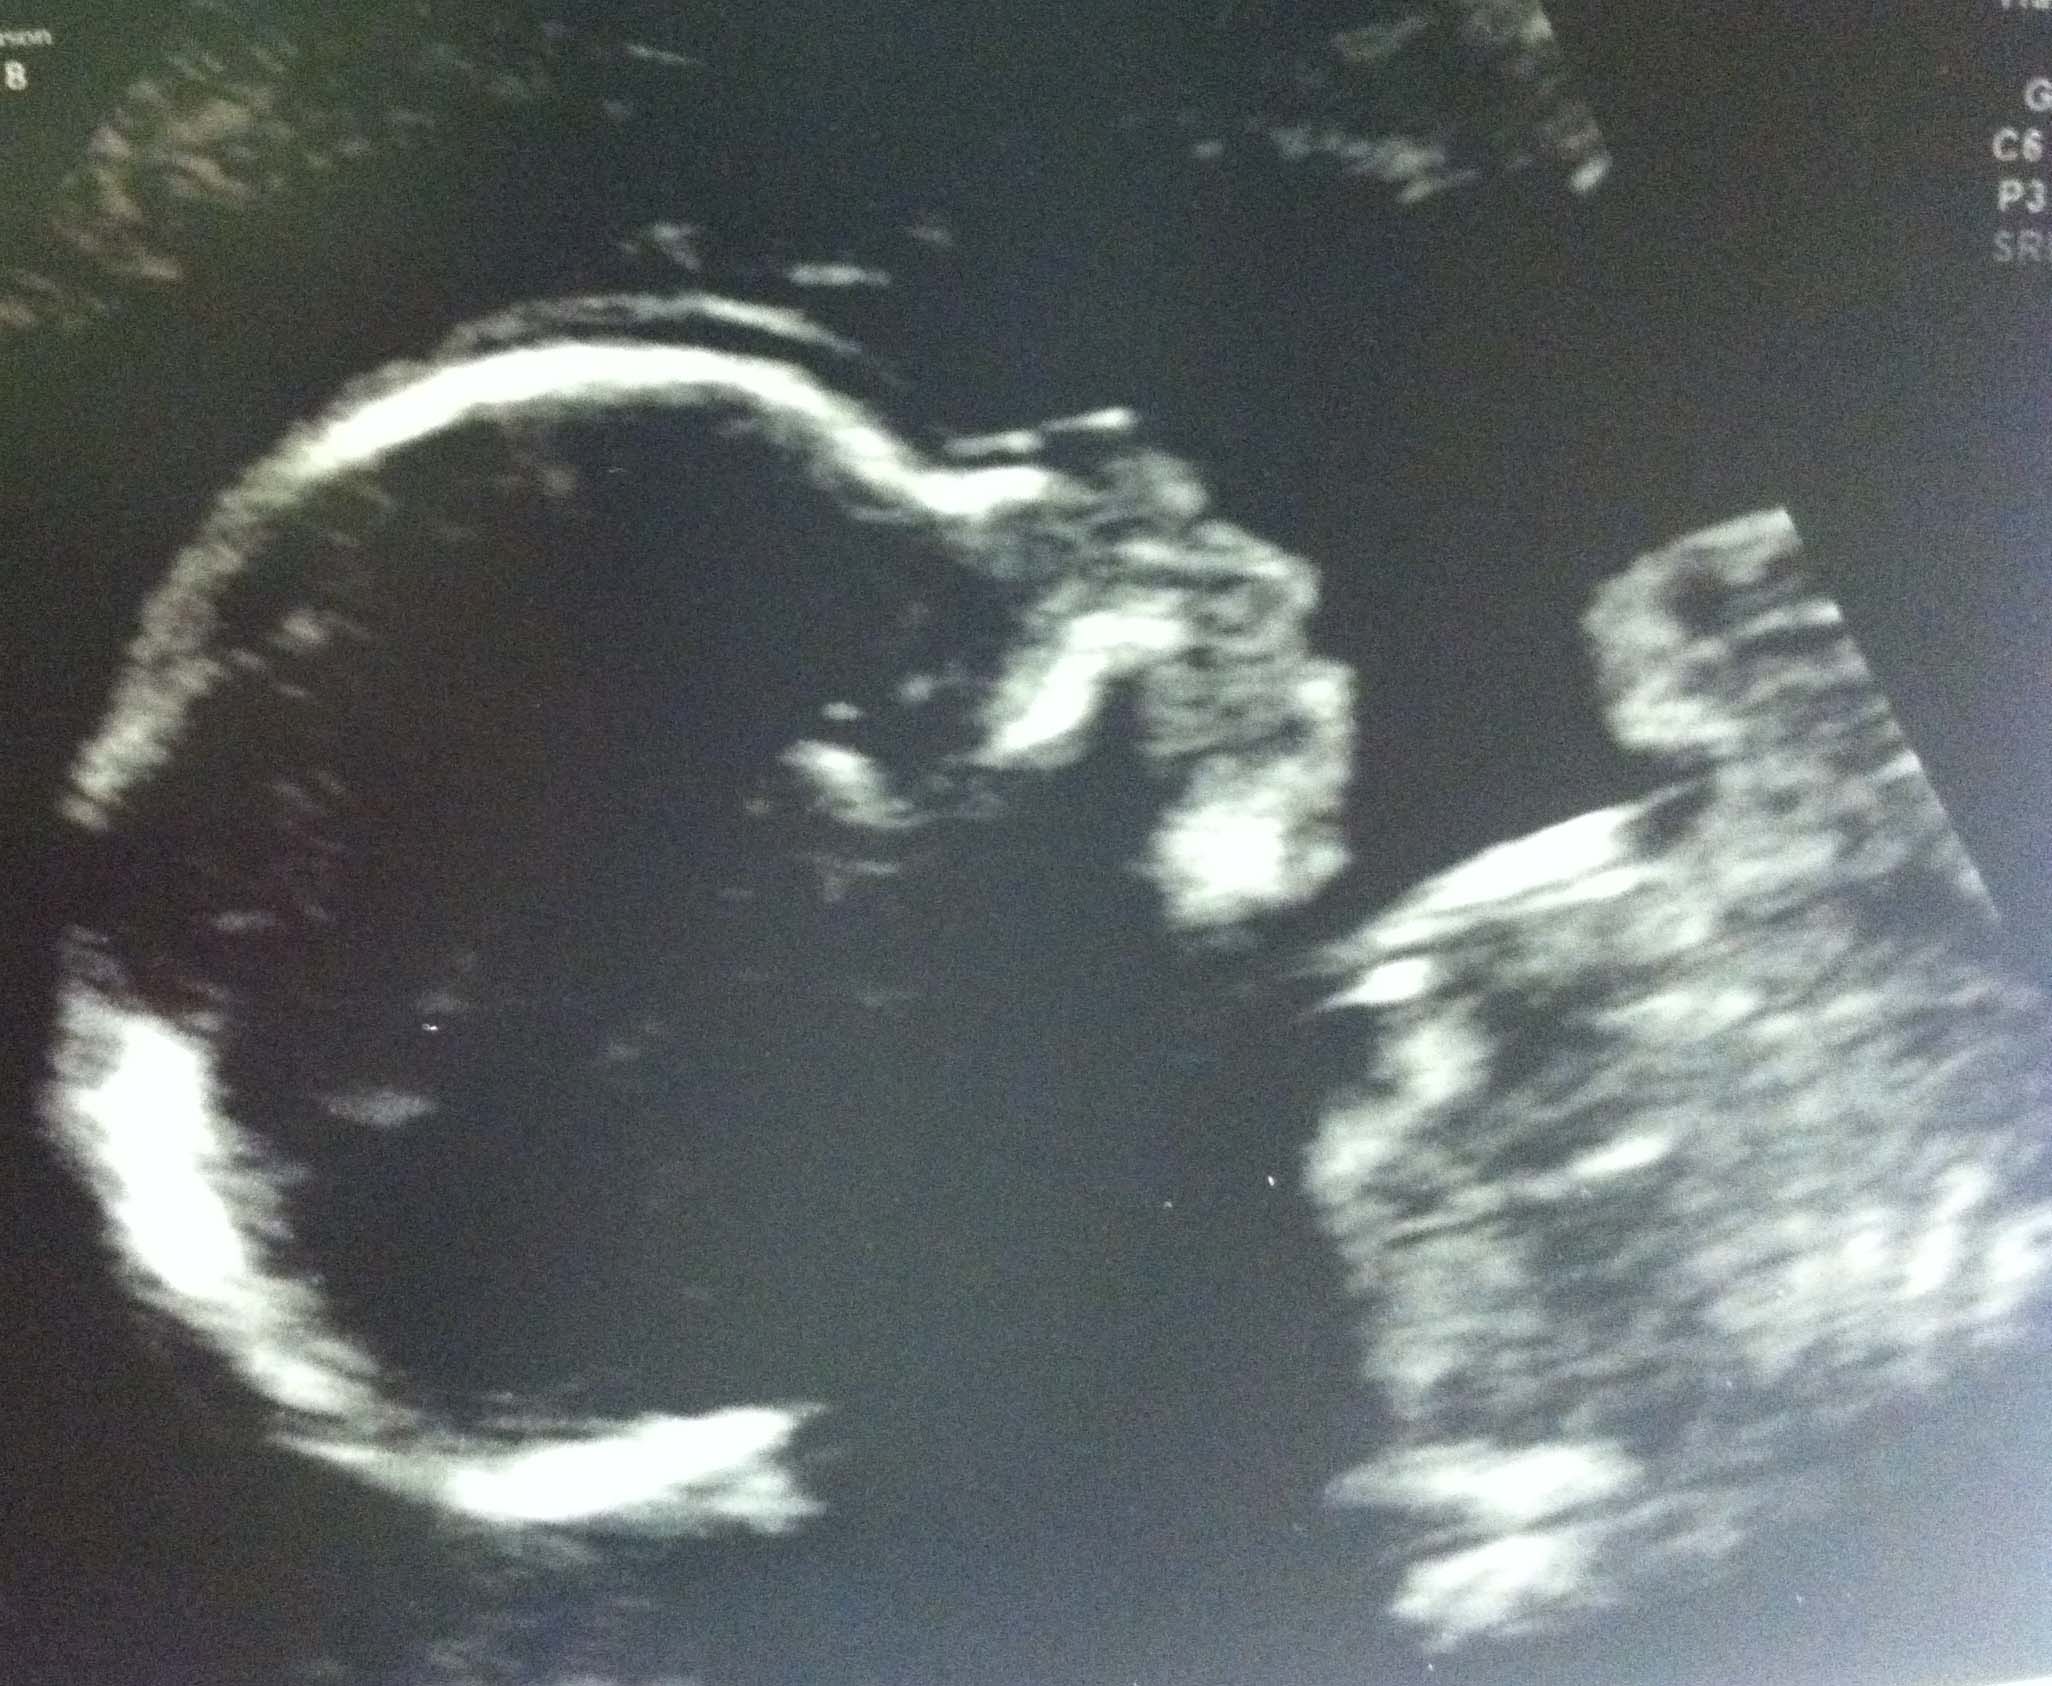

Here's a picture of the kid:

I've been seeing the rash of anatomy scan posts and thought, "Screw it, I'll join the party!" Given my age (42) and all the other jazz that makes my pregnancy a bit more of an medical "adventure," I figure all news is good news. So, after a 2-hour long Level II anatomy scan with our high risk MFM (seriously--two hours; my back was killing me), little William checked out as completely healthy, and everything looked great. I still have the pictures of my older son's 20-week anatomy scan on my phone and it was fun to look at them side by side--they look a lot alike! I spoke with the MFM at length, and he said that, as there were no abnormalities in the scan, he didn't recommend an amnio (he spoke about risks to the baby versus any answers we might get at this stage of the game, and it didn't seem worth it to him; I was wavering--again, I am old--but finally realized that his opinion was probably the right one).